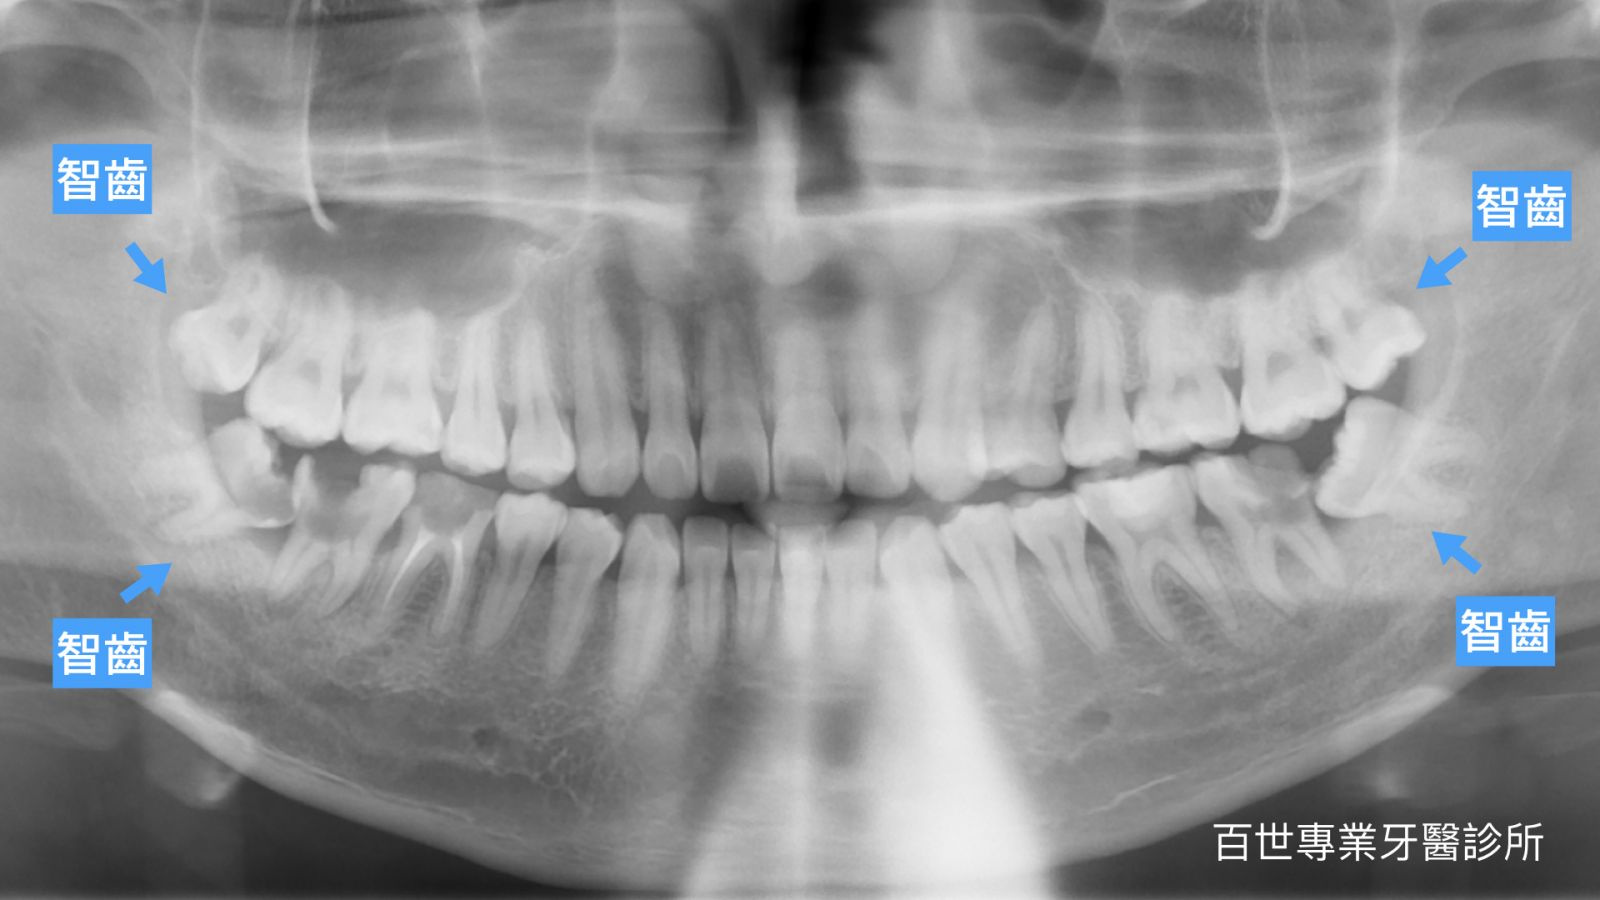

- 避免「含齒囊腫」等隱性傷害: 即使智齒完全包在肉裡不痛,長期也可能病變為「含齒囊腫」,嚴重時需手術摘除部分顎骨。透過 X 光評估能提早防範隱形風險。

為降低嘴唇發麻或口鼻相通等風險,術前一定會拍攝 X 光,並由醫師進行嚴謹影像評估。透過影像確認牙齒、神經與骨骼的距離,並與患者充分溝通,確保手術安全。